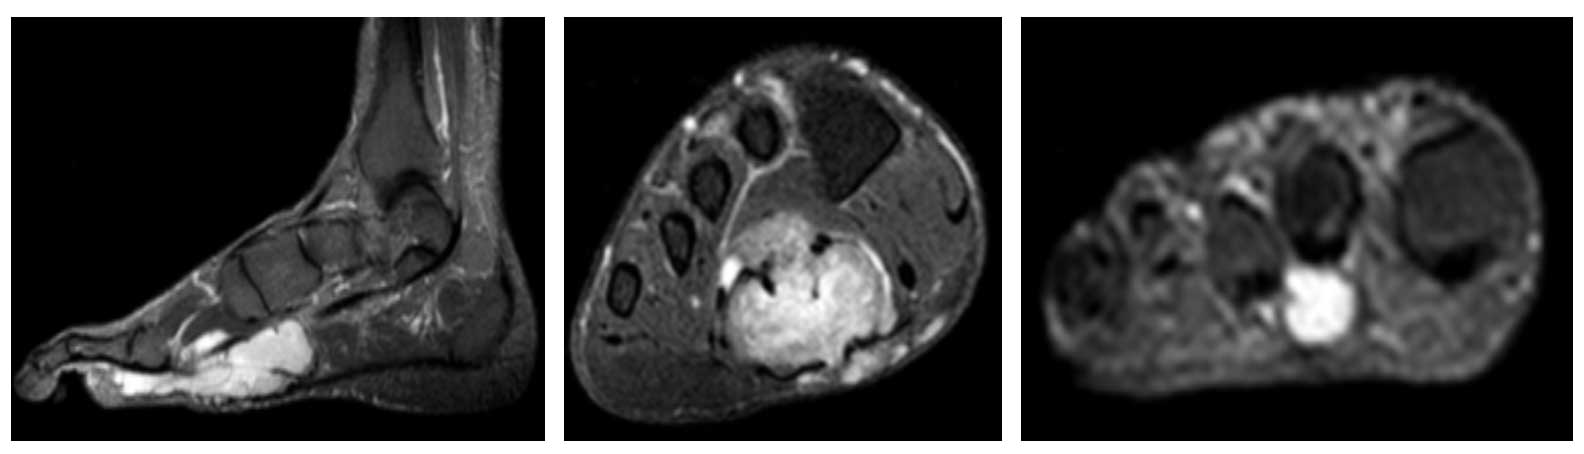

Vaka 39: Ayak Yumuşak Doku Yerleşimli Kondrosarkom

Yapılan MR ve diğer radyolojik incelemelerde yumuşak doku kaynaklı kondrosarkom ile uyumlu lezyon saptandı

Ameliyat Öncesi: MR’da ayak tabanında yerleşmiş, kemik dokuyu invaze eden düzensiz sınırlı tümör dokusu görülmekte.